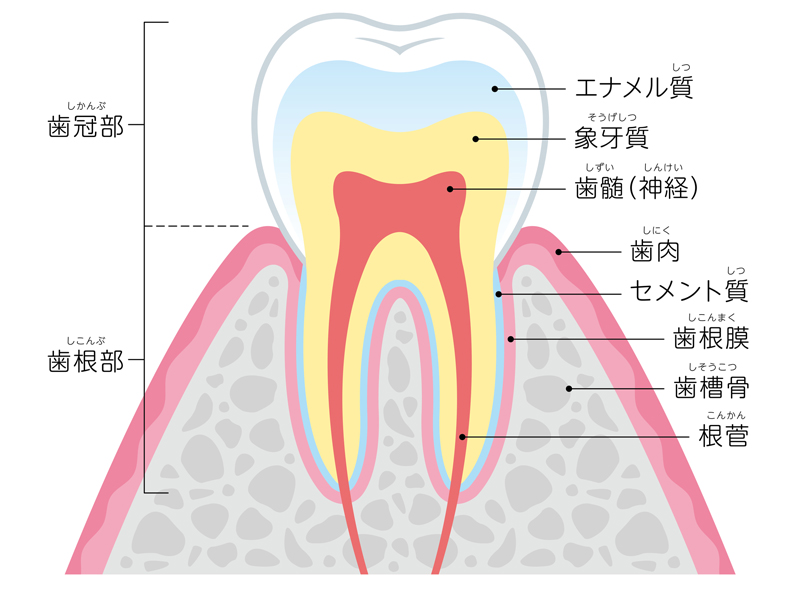

歯の神経は、正式には「歯髄(しずい)」と呼ばれ、血管と神経が入り混ざった状態で存在しています。

歯髄には、歯に栄養や水分、酸素を運んだり、免疫などの防衛反応を伝達するなど重要な役割があり、そのおかげで歯はツヤや丈夫さを保つことができます。

そのため、歯の神経がなくなってしまうと、栄養分や水分が歯に行き届かなくなってしまい、まるで枯れ木のように脆く、割れやすくなってしまいます。

そうすると、必然的に歯の寿命も短くなりますので、将来的に歯を失い、義歯やブリッジなどの補綴手段(歯を補う手段)が必要となり、結果的に治療にかかる費用も大きくなってしまうケースが多々あるのです。